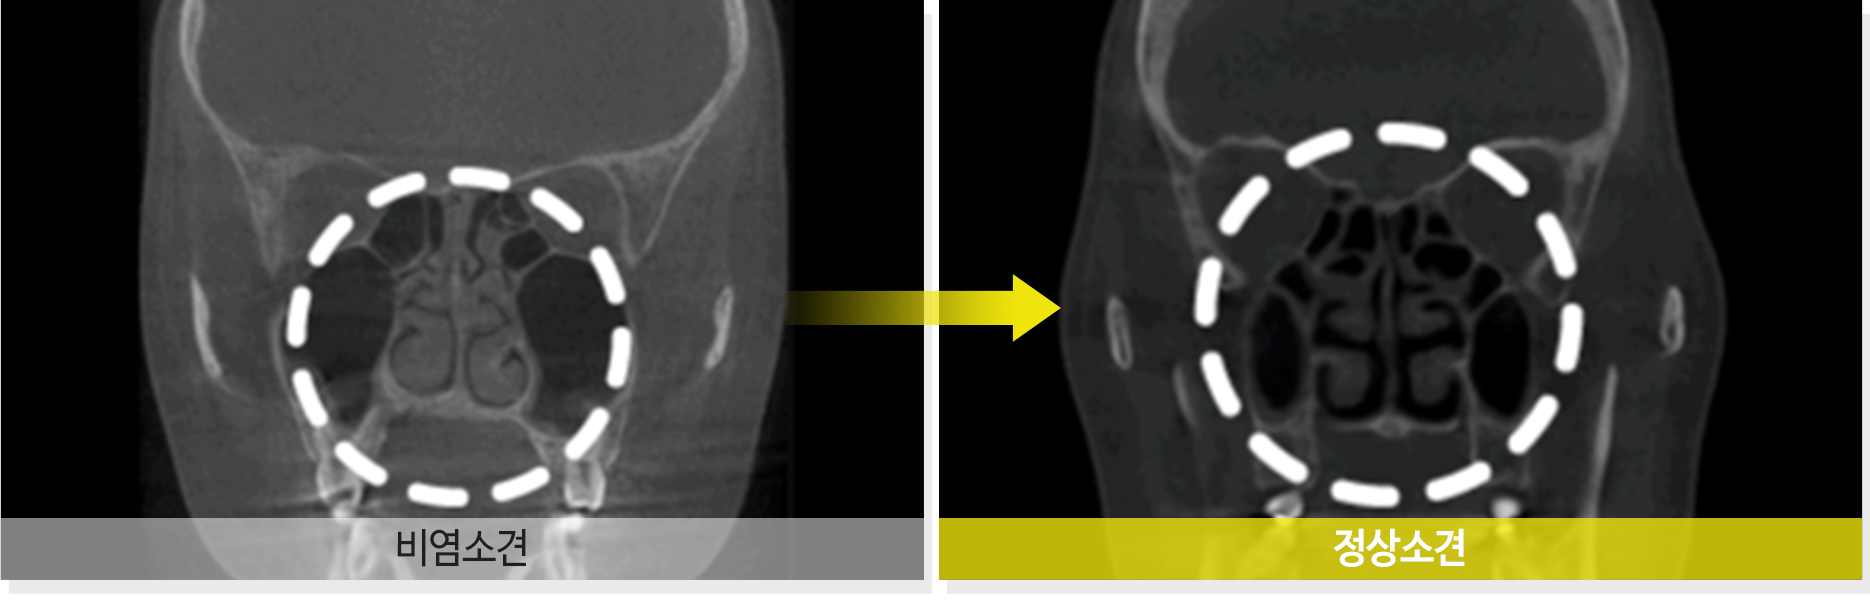

알레르기성 비염이라면 재발할 우려가 있지만

비알레르기성 비염의 경우에는 재발할 확률이 적습니다.